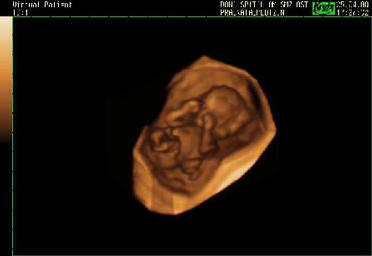

Referring to a bill supported by Rick Perry that would allow women to see an ultrasound of their unborn baby before going through with an abortion, Planned Parenthood president Cecile Richards said the following. Keep in mind that Planned Parenthood routinely does ultrasounds anyway to gauge the length of pregnancy and rule out ectopic pregnancies. Women are just not allowed to look at the screen or discouraged from doing so.

Apparently, seeing an ultrasound before an abortion is something that Planned Parenthood considers dangerous– perhaps if fewer women choose to have abortions, it would cut into the organization’s profits.

Read about Abby Johnson, Planned Parenthood director, whose change of heart happened after watching an abortion on the ultrasound.